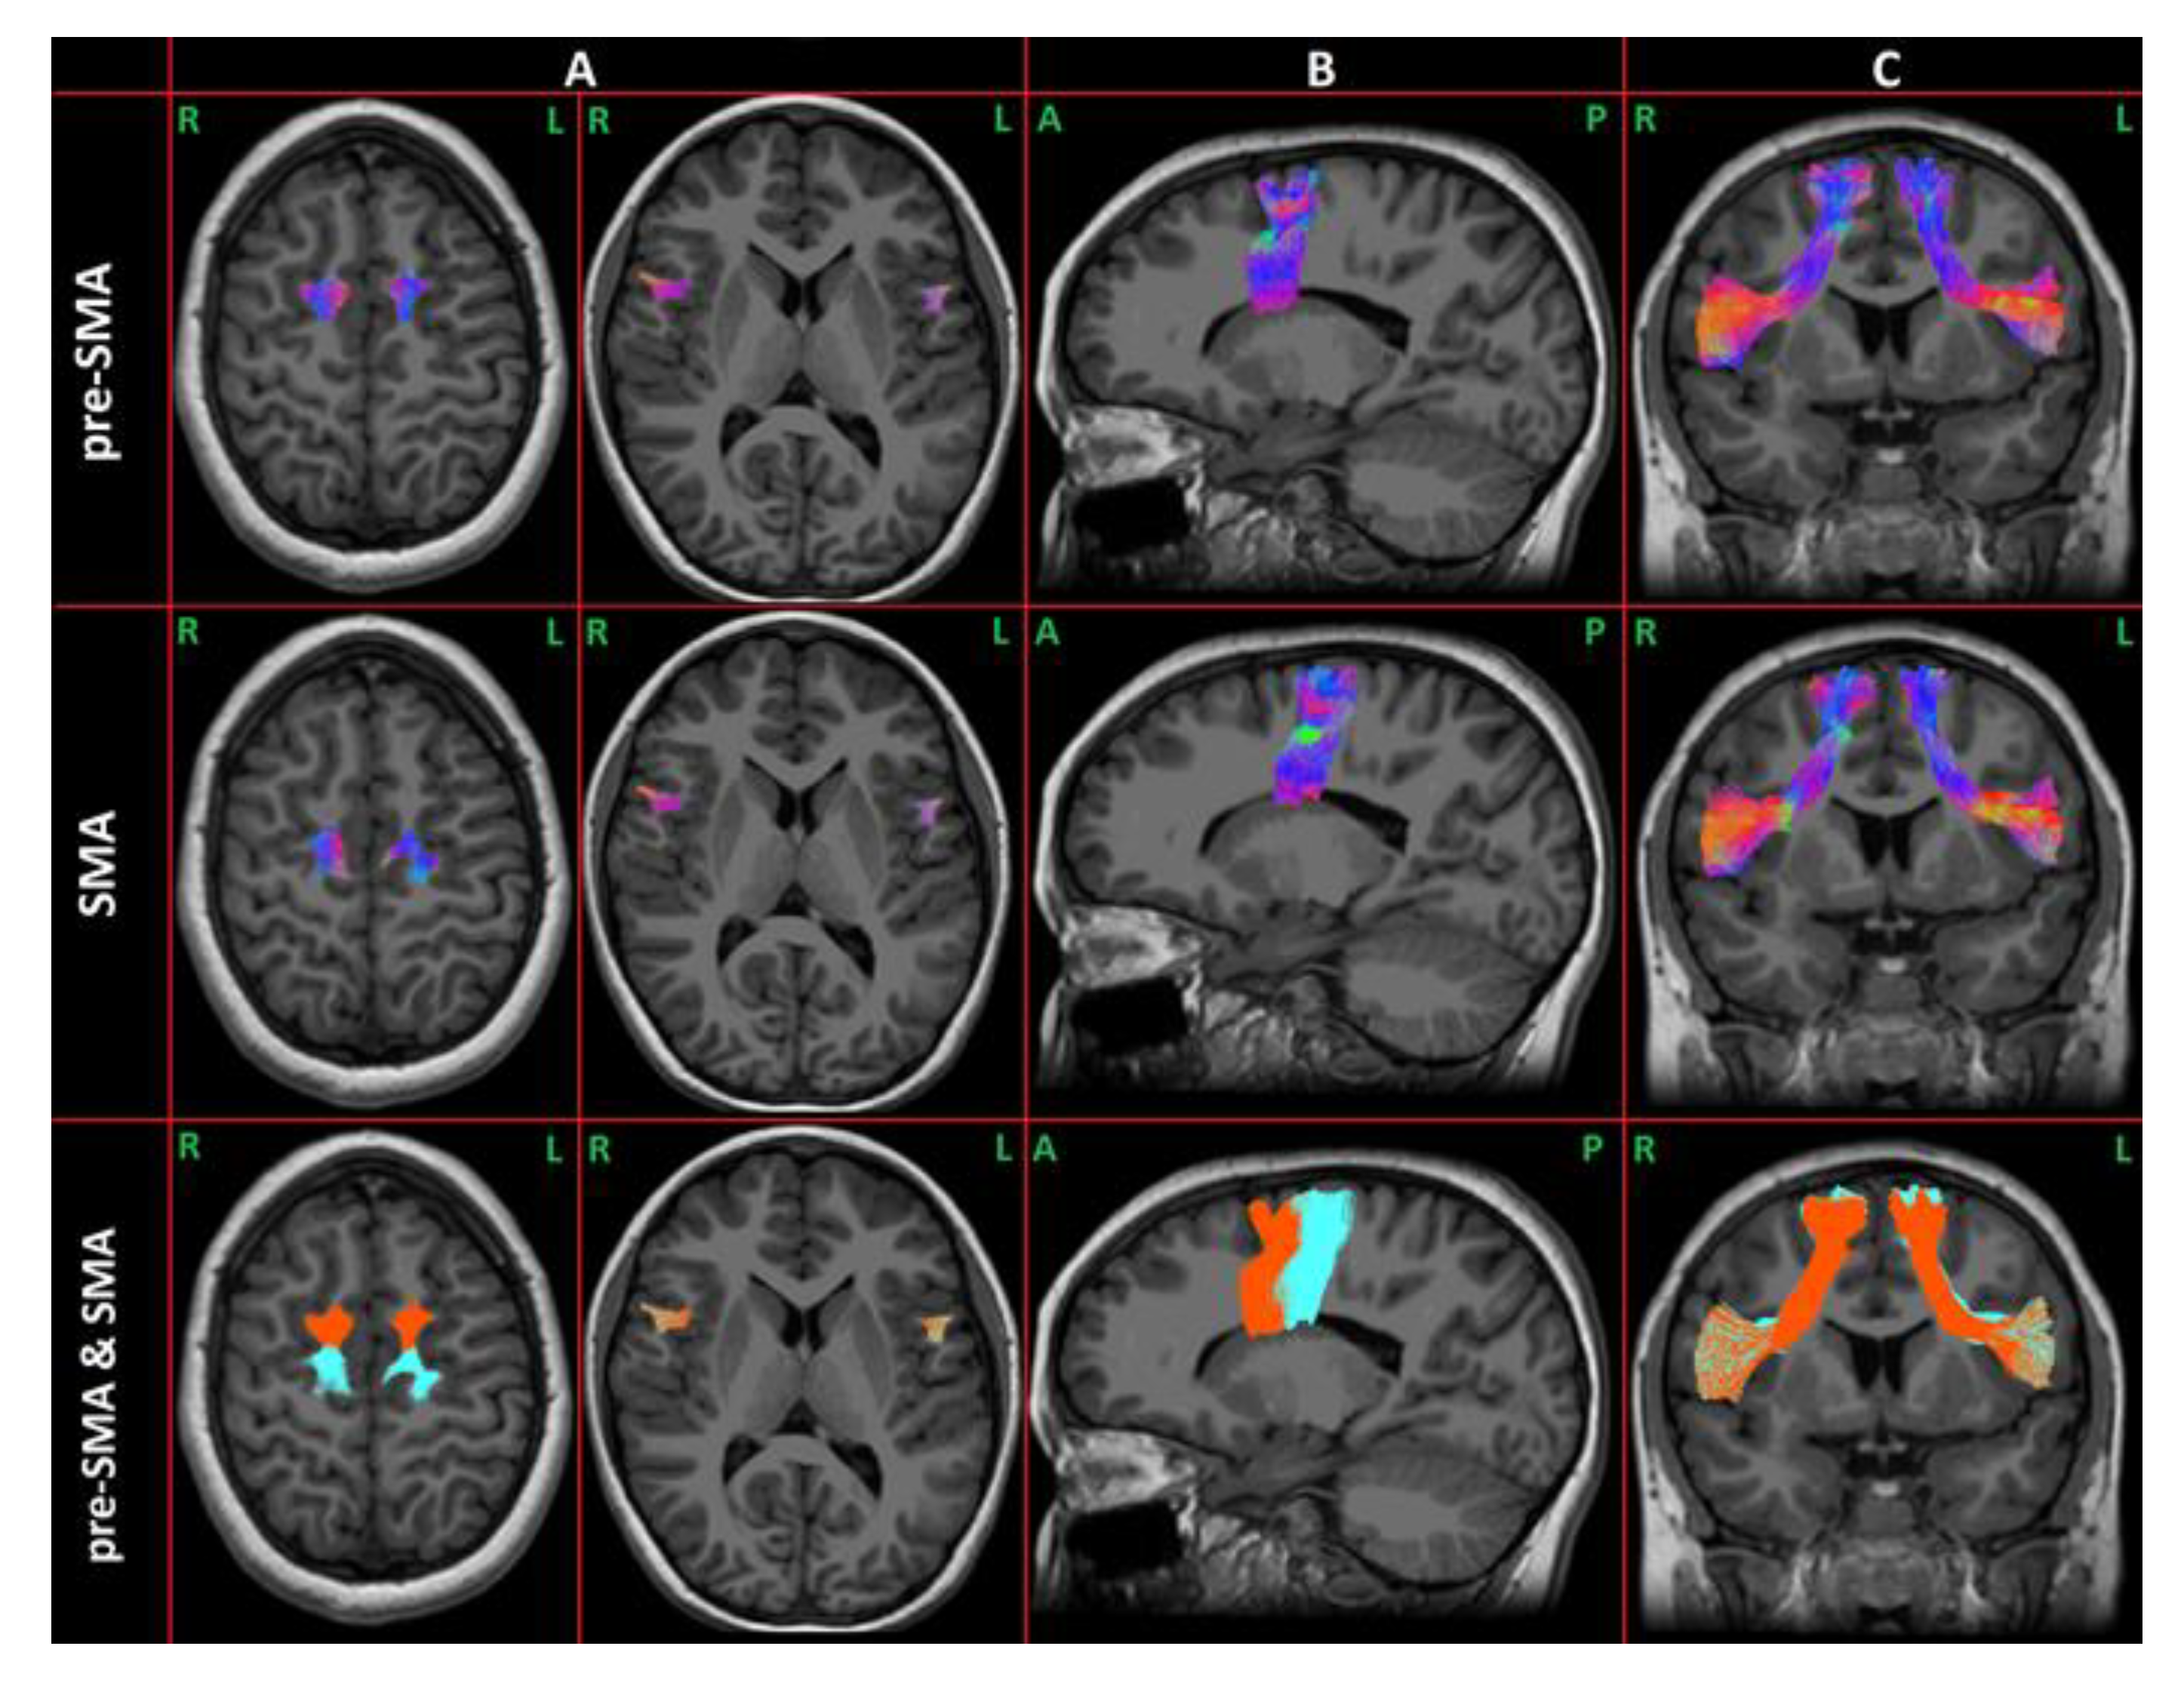

Each component of the FAT was extracted from each hemisphere of each CAS and TD subject. An example case is shown in Figure 2.

Figure 2.

Example of the FAT: The first two rows represent the preSMA and SMA components. The direction of the tract is coded using RGB for the XYZ direction: red indicates the left–right direction, green the anterior–posterior direction, and blue the superior–inferior one. In the last row are overlapped both the FAT components (orange for preSMA and light-blue for SMA). Panel (A) shows the top and the bottom of the tracts in the axial plane. In panels (B,C), the projections of the FAT in the sagittal and coronal planes are respectively represented.